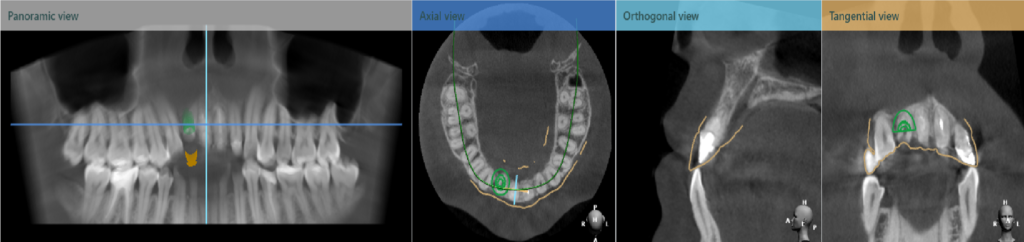

數位導引板是依每人口內狀況而全客製化設計而成,需要口掃機搭配數位排牙與設計軟體、電腦斷層,3D列印製作而成,可以避開患者的神經、血管、上顎竇等解剖構造,使植牙手術更能植入正確的植體位置,更加安全也提升植牙成功率,對植體的精準度要求更高!

理想的植體放入位置要考量3D位置,如植體與鄰牙之間的距離、未來植體放入的深度以及未來假牙接出來的方向等。

在植牙手術中也是如此,因此為了達到最精準的鑽洞,會使用叫做「手術導引版」的工具做一個輔助。

在手術過程我們的鑽針靠著導引版的方向鑽入,就可以把植體植入到接近理想位置。